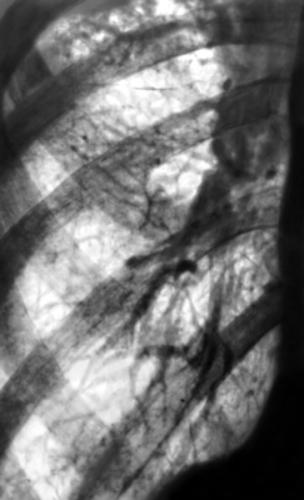

Рентгенологическая картина полиморфная, потому что показывает проявления не только самого пневмосклероза, но и сопутствующих болезней: эмфиземы легких, бронхоэктатической болезни, бронхита с хроническим течением и проч. Типичные петлистость, усиления и деформация легочного рисунка по ходу бронхиальных разветвлений, поскольку уплотняются бронхиальные стенки, имеют место склероз и инфильтрация перибронхиальной ткани.

Бронхография показывает девиацию или сближение бронхов, сужение и отсутствие мелких бронхов, деформацию стенок. Спирография является эффективным диагностическим методом при подозрении на пневмосклероз, выявляет уменьшение ЖЕЛ, ФЖЕЛ, индекса Тиффно.

Над пораженной зоной физикальные обследования обнаруживают ослабление дыхания, сухие или влажные хрипы, притупление перкуторного звука. Достоверным диагностическим методом является и исследование легких. Даже если симптомов нет, рентген помогает обнаружить изменения при их наличии, характер их, распространенность, то, насколько они выражены. Более точно оценить состояние нездоровых зон ткани легких могут магнитно-резонансная томография, бронхография, КТ легких.

Рентгенограмма показывает такие изменения пораженного легкого:

- уменьшение его в размерах

- усиление легочного рисунка по ходу разветвлений бронхов

- легочный рисунок сетчатый и петлистый по причине деформации стенок бронхов

- «сотовое легкое» в нижних отделах

Флюорография при пневмосклерозе

При любых жалобах на кашель и любую дыхательную симптоматику, нужно пройти обязательно флюорографическое обследование органов грудной клетки. Каждый год в целях профилактики и раннего выявления пневмосклероза, туберкулеза и прочих подобных заболеваний все лица от 14 лет должны проходить медицинский осмотр. При пневмосклерозе снижается жизненная емкость легких, низкий индекс Тиффно (который является показателем проходимости бронхов).